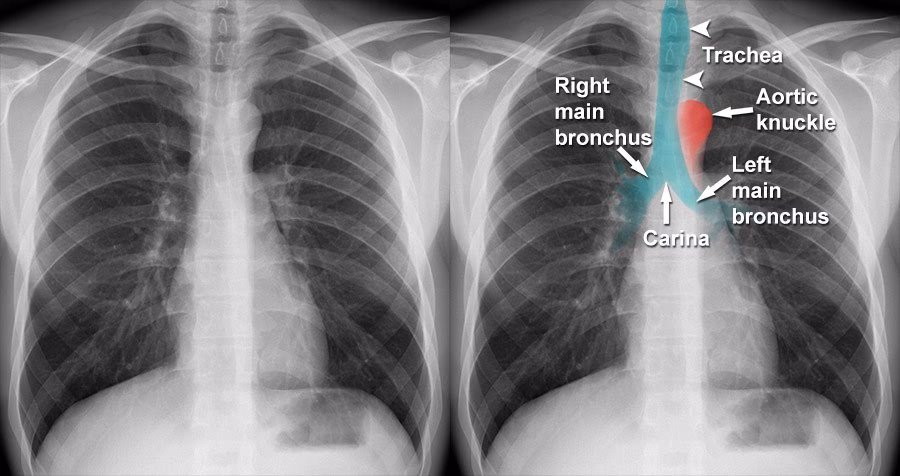

Røntgenundersøgelse ved Akut Bronkitis: Sjældent Nødvendigt

For en patient med klassiske symptomer på simpel, ukompliceret akut bronkitis er en røntgenundersøgelse af brystkassen sjældent nødvendig. Lægen stiller typisk diagnosen baseret på sygehistorien og en fysisk undersøgelse, hvor der lyttes på lungerne (stetoskopi). Men der er situationer, hvor en røntgenundersøgelse bliver et vigtigt diagnostisk redskab.

På et røntgenbillede af en person med akut bronkitis vil billedet oftest se helt normalt ud. I nogle tilfælde kan man se en let fortykkelse af bronkiernes vægge. Dette er dog et uspecifikt fund, hvilket betyder, at det også kan ses ved andre tilstande og ikke er et definitivt bevis på bronkitis.